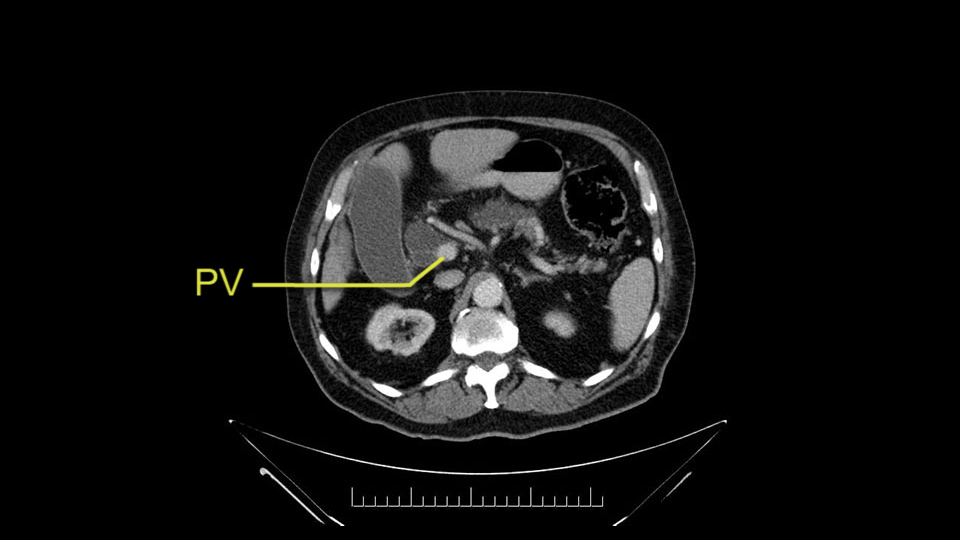

The next item that I would look at: the issue would be the vessels and usually start at the portal vein, watch the portal vein, follow it down, down-down-down to the neck of the pancreas - which is here - and there’s no impingement by tumor, which is great. The SMV and the splenic vein, which is here. The splenic vein junction is normal, which is great.

The next thing we always evaluate, although we do not expect invasion to the portal veins in this case, we must always trace the path of the portal vein, in both directions, from top to bottom. The splenoportal confluence and the superior mesenteric vein, which in this case does not appear to be compromised.

Por otro lado, siempre evaluamos -aunque en este caso no esperamos que haya invasión de los vasos portales-, siempre hay que hacer el recorrido de la vena porta, en ambos sentidos, de arriba hacia abajo; el confluente esplenoportal y la vena mesentérica superior, que en este caso no aparentan estar comprometidos.